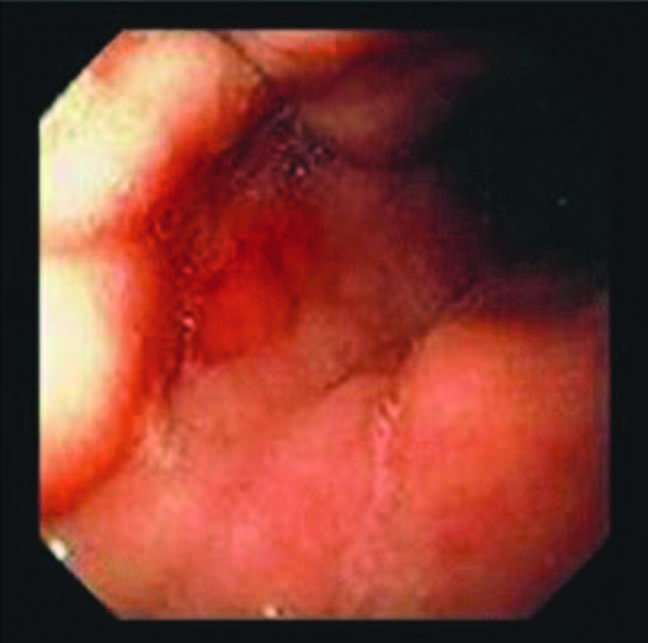

Chinoise de 40 ans buvant beaucoup de saké, AEG. endoscopie oeso-gastro-duodénale, que voit on?

A

Linite gastrique: muqueuse normale mais gros plis rigides, l’estomac ne prend pas l’insufflation.